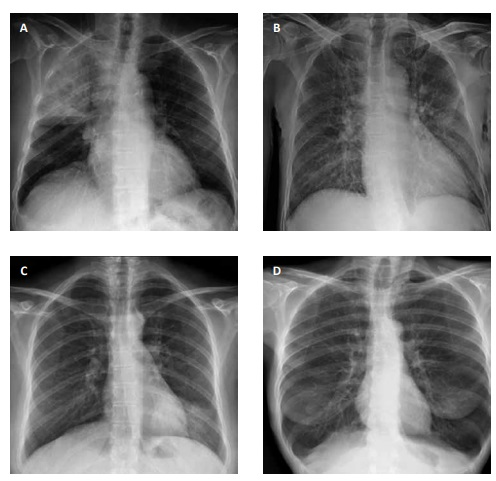

Uma mulher de 63 anos de idade, obesa, hipertensa, diabética e dislipidêmica, em uso irregular de anlodipino,

metformina e sinvastatina, compareceu ao pronto-socorro com relato de tosse, febre aferida de 38,2 oC, coriza, mialgia e

espirros há três dias, porém, nos últimos dois dias também percebeu edema de membros inferiores e dispneia importante que

a fizeram procurar o pronto-socorro. Ela relatou que realizou um teste recente na farmácia, influenza A positivo. Na admissão,

apresentou: temperatura de 37,7 oC; glasgow 15; PA 180 x 110; FC 118 irpm; e FR 26 irpm. A paciente segurava-se à grade do

leito devido à ortopneia, havia presença de estase jugular, pulso com ritmo irregular e ausculta com estertores de base até terço

ápice bilateralmente. O eletrocardiograma da paciente apresentou: ausência de onda P; RR irregular; QRS estreito; e

FC 118 bpm.

Assinale a alternativa que corresponda ao exame de imagem compatível ao caso clínico apresentado.